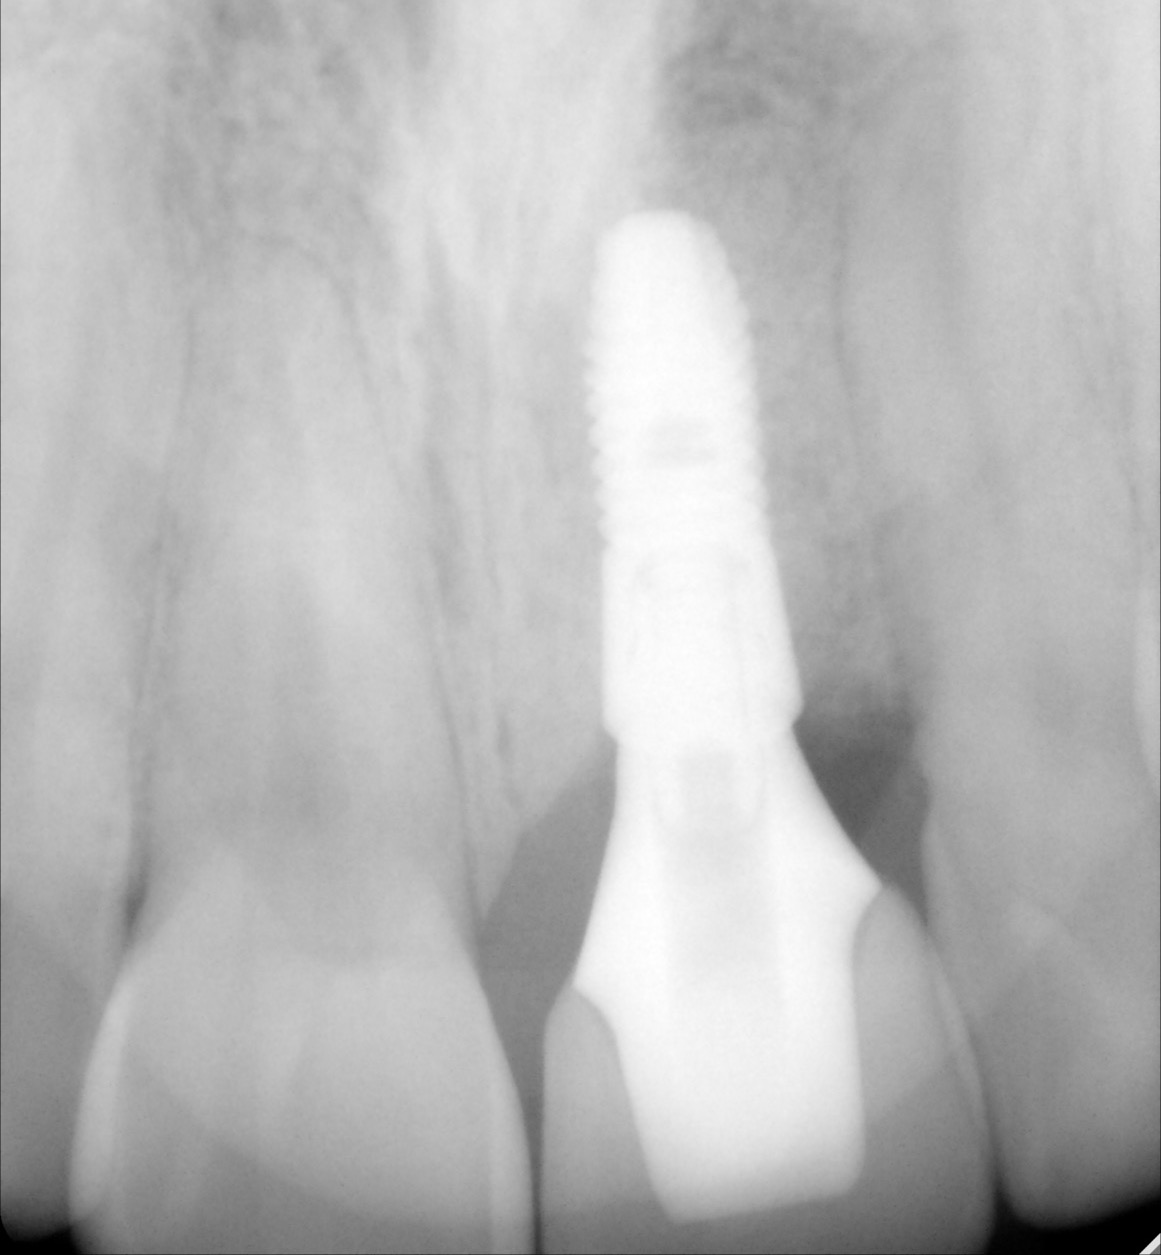

A dental implant is a titanium post that serves as a replacement for the root of a missing tooth. The implant is surgically inserted into the jawbone, where it is fused with the bone as the latter heals over time in a process called osseointegration. Once integrated, the implant becomes a sturdy foundation for one or more artificial teeth.

- Implant post: The titanium screw that is placed into the jawbone.

- Abutment: The connector piece that attaches the implant post to the restoration.

- Restoration: The final artificial tooth or teeth, designed to look and function like natural teeth.